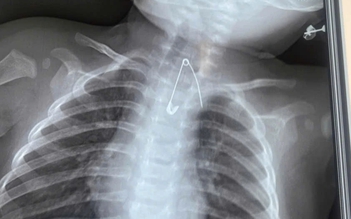

2 trẻ nguy kịch vì nuốt dị vật